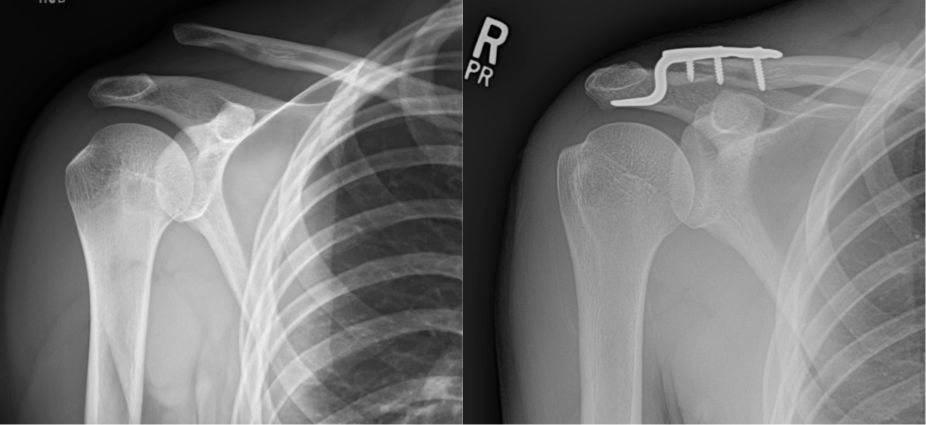

Clavicle fractures occur most frequently after a direct fall on the shoulder. They are especially common in young males. Dirt biking accidents are a frequent mechanism. They present with pain and swelling over the clavicle. In general, greater than 2 cm of shortening or 100% displacement increases the chances of non-union, decreased shoulder strength, decreased endurance, and altered scapular mechanics with pain. Many clavicle fractures can be treated without surgery; however, patients with greater than 2 cm of shortening or greater than 100% displacement typically have better short term outcomes with surgical fixation.

Clavicle radiographs demonstrating a multi-fragmented right clavicle fracture (left image), treated with open reduction and internal fixation (right image)